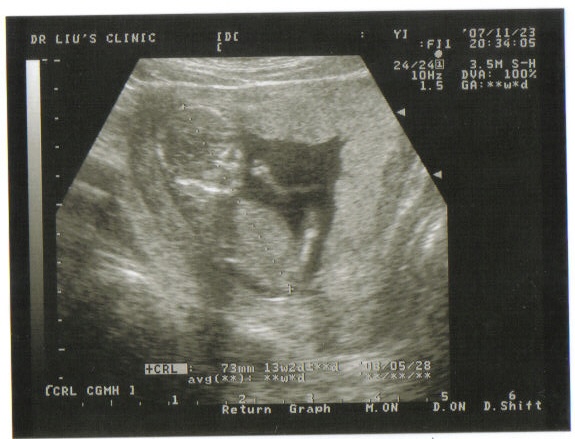

大家看的出來這是什麼嗎~~(其實在我沒懷孕之前~大家的超音波我實在是有看沒有懂啊~)~

所以為了方便大家了解~這團黑黑的到底是什麼~~我特別做了圖解~~

大家看的出來這是什麼嗎~~(其實在我沒懷孕之前~大家的超音波我實在是有看沒有懂啊~)~

所以為了方便大家了解~這團黑黑的到底是什麼~~我特別做了圖解~~